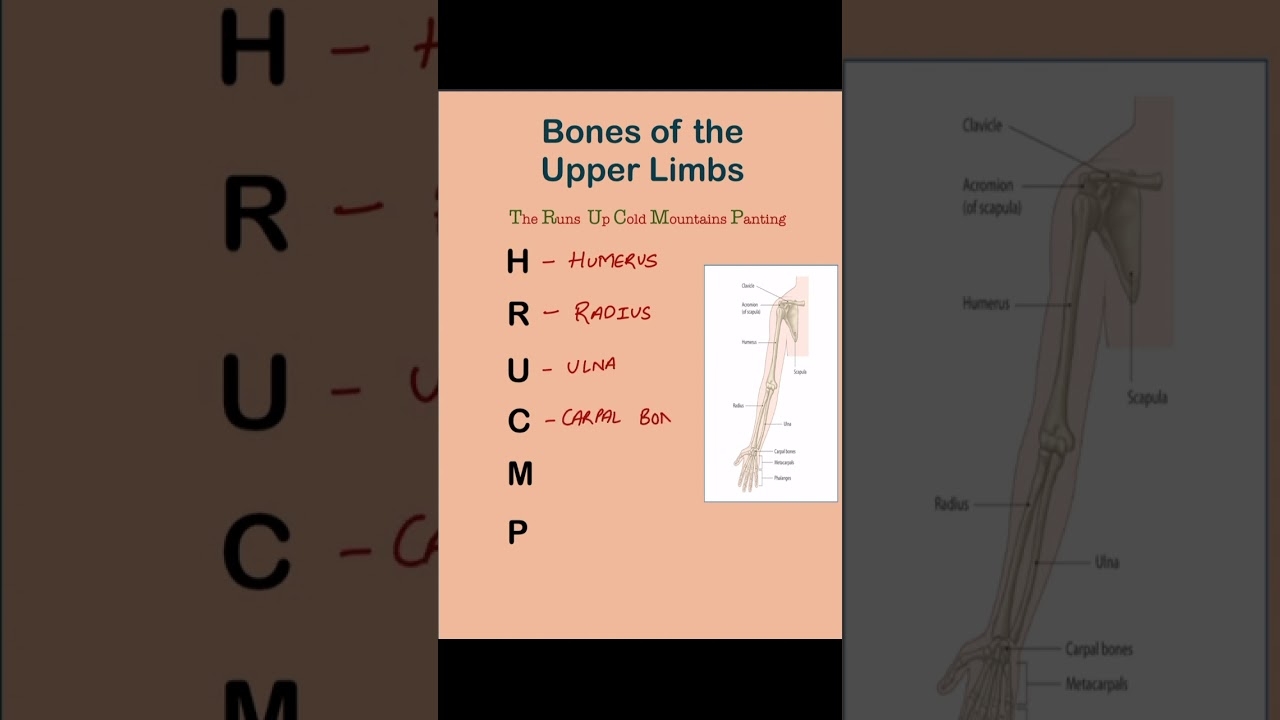

arm bone crossword clue

Target Arm Bone Crossword Clue: Humerus

Of An Arm Bone NYT Crossword Clue